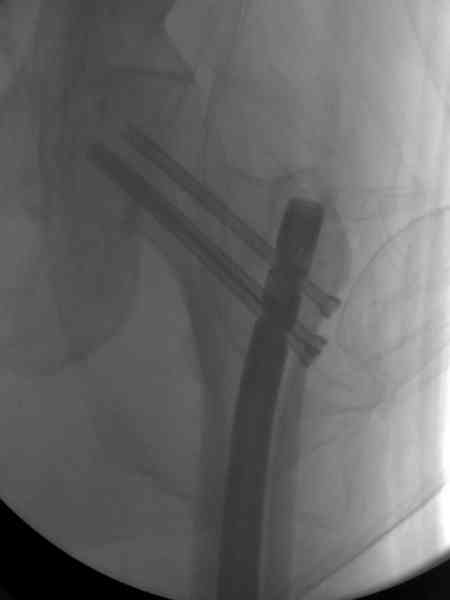

В первый же день произведено антеградное штифтованием DePuy Trochanteric Nail.

На второй день (7) обнаружен пропущенный перелом,

сделаны Компьютерная Томограмма

и проведены шурурпы через и спереди штифта без удаления.

Послеоперационные снимки